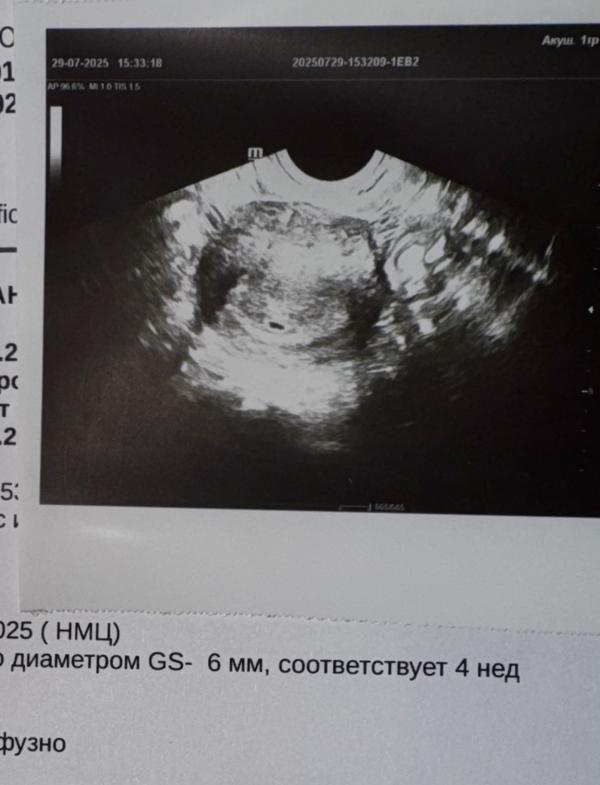

Все приложения отсчитывали с 21.06.25(1й день последних мес) и показывало 6ю неделю, но из-за сбоя после приема Фертины и нерегулярного цикла, сегодняшнее УЗИ показало еще совсем крошку, приблизительно 4 недельки))

У меня именно акушерский не 5+ как считается, а 4 недели) эмбриональный совсем кроха))